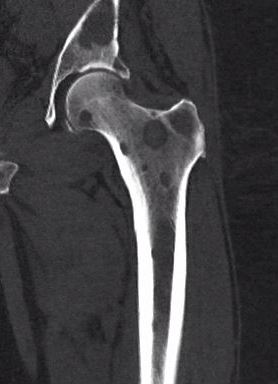

X-ray

1. Punched out lytic lesions

- axial and appendical skeleton

- widely disseminated

- soap bubble appearance

- no sclerotic reaction

2. Diffuse osteopenia

- in 15% to 25% of patients, no discrete lysis occurs

- diffuse osteopenia and osteoporosis are the only skeletal manifestations

3. Vertebrae Plana

4. Pathological Fracture

5. Pepper pot skull